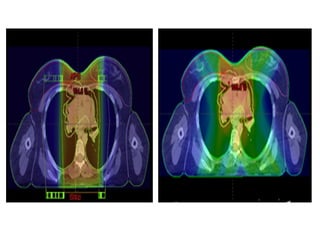

Color-wash dose distributions

for three different plans for

treating mediastinal Hodgkin

lymphoma: axial sections (top)

and sagittal

sections (bottom) for

conventional photon three-

dimensional conformal

anteroposterior/posteroanterior

fields (left), intensity-modulated

radiation

therapy photon (middle), and

anterior proton field (right).

Green outline, esophagus; red

outline, heart; pink outline,

breasts; blue outline, clinical

target volume.